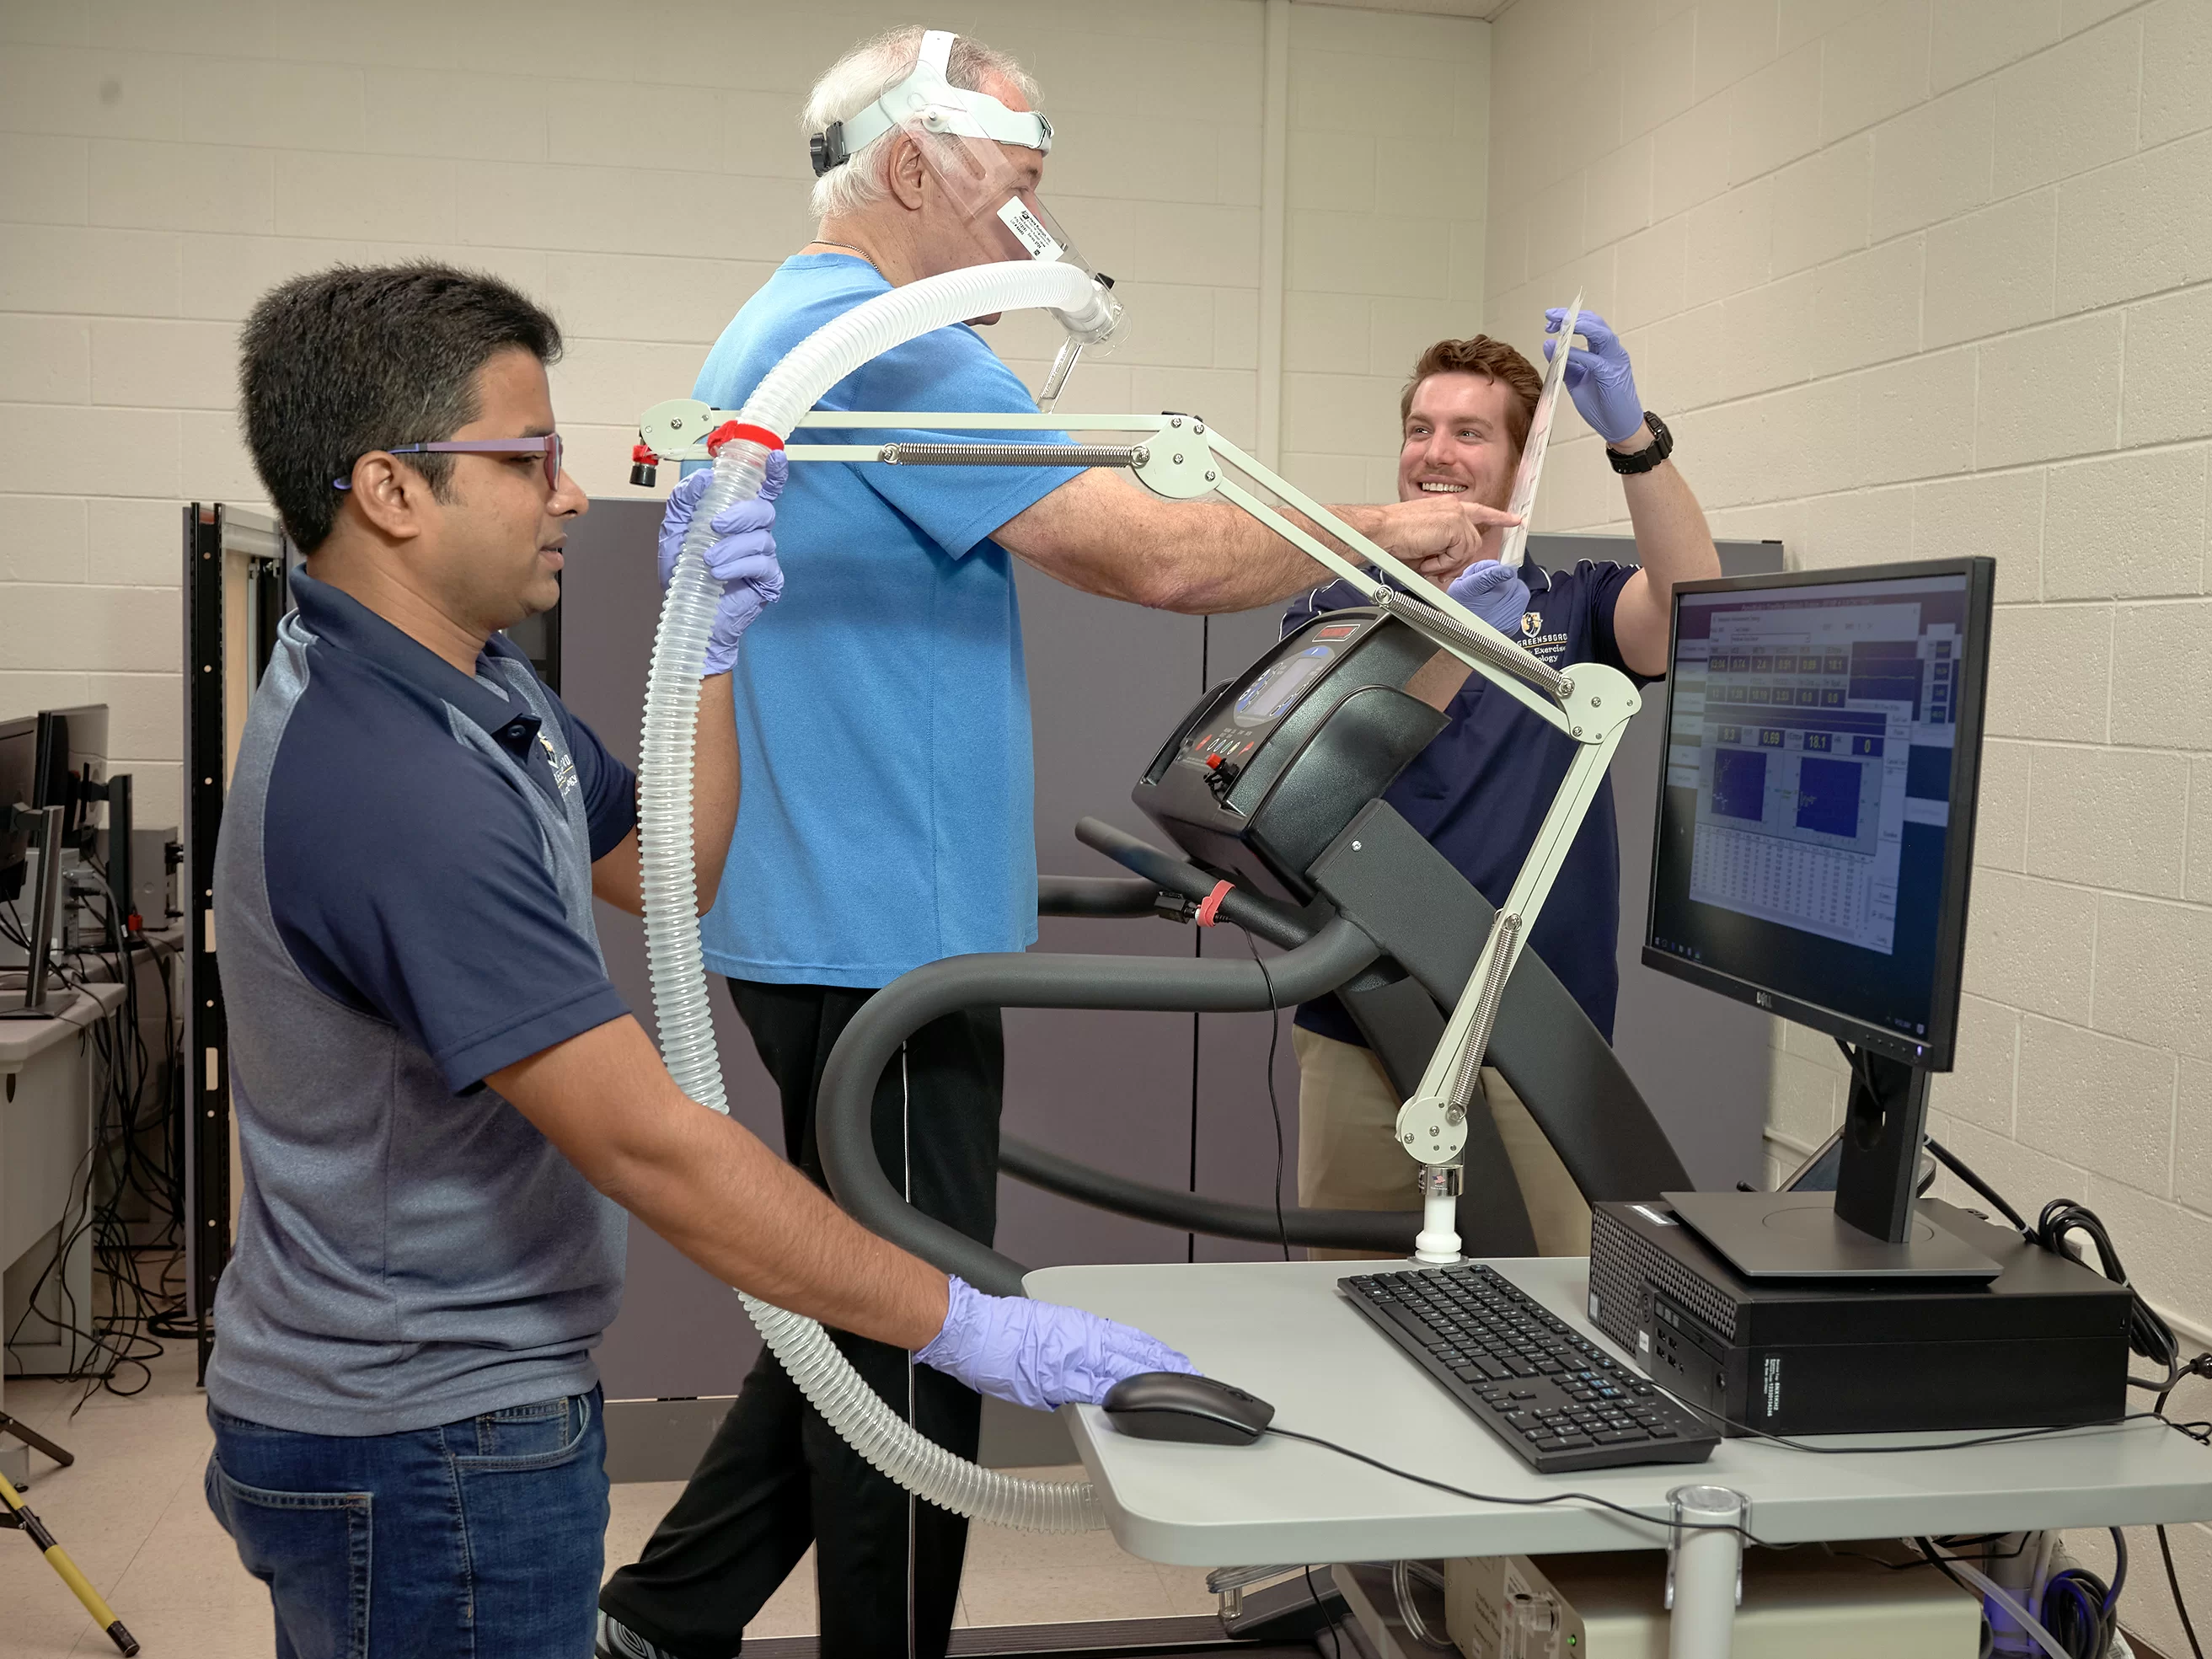

Dr. Jennifer Etnier, professor of kinesiology, is exploring how exercise may delay the onset of Alzheimer’s. In one large research study with $3.4 million in National Institutes of Health funding, she recruited middle-aged and older adults who may have a genetic risk of Alzheimer’s disease.

MRI scans of the volunteers’ brains are one of the ways Etnier is assessing the impact of exercise on the volunteers’ Alzheimer’s risk. Among people with the highest genetic predisposition for Alzheimer’s, brain changes can be detected as early as in someone’s 40s. Etnier hopes to be able to assess whether exercise delays those harmful changes in brain structure.

“From the first day of my doctoral program, I was excited to use the MRI scanner,” says Dr. Alexis Ganesh, who worked with Etnier (photo 1) and UNCG’s machine as a grad student and then as a postdoc.